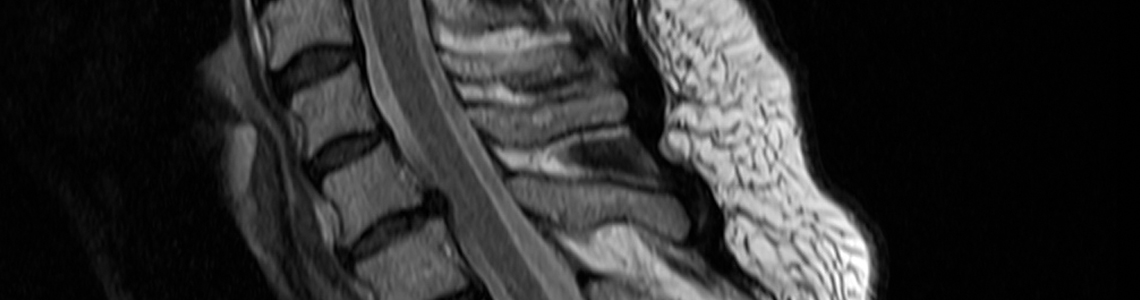

Die Kernspintomographie hat besondere Vorteile bei der Untersuchung von nicht-knöchernen Strukturen wie Weichteilen, Gelenken sowie der Wirbelsäule mit Rückenmark und dem Gehirn. Auch innere Organe (mit Ausnahme der Lunge) lassen sich sehr gut mit der MRT untersuchen.

Die Vorteile gegenüber der Röntgen-Computertomographie sind eine bessere Abbildbarkeit von Weichteilstrukturen (Bandscheibe, Sehnen, Bänder), eine bessere Darstellbarkeit von Durchblutungsstörungen und Tumoren im Gehirn sowie eine sehr gute Darstellung des arteriellen und des venösen Blutgefäßsystems (MR-Angiographie) bei speziellen Fragestellungen wie Stenosen oder Aneurysmata.

- Wirbelsäule